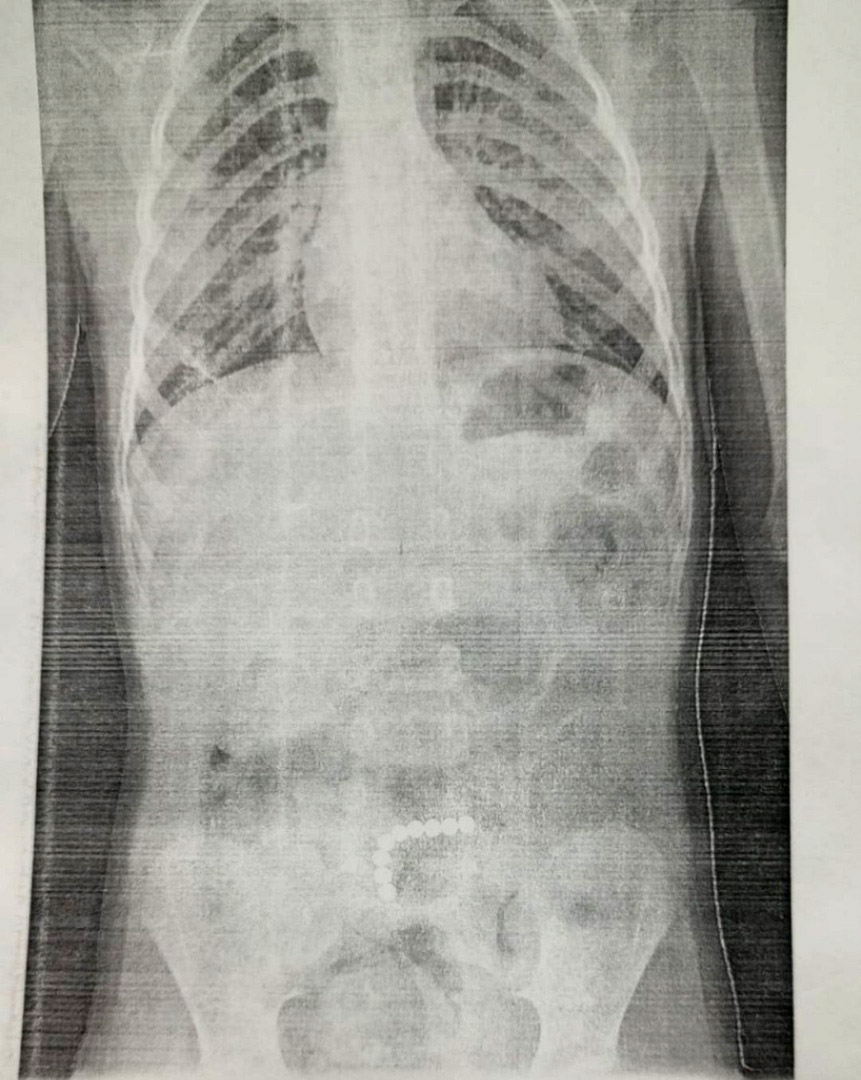

Магнитные шарики на рентгене: Интересные находки

Раздел: Картинки на заметку